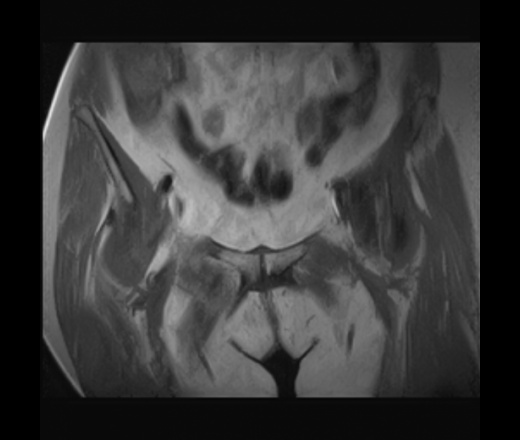

МРТ тазобедренный сустав (срочно)

Пациентка 1944г. р. Жалобы на боль области сустава в течении месяца. Температуры не отмечала. Серьезных травм со слов не было. Внешний осмотр новых данных не дал.

Дайкомы пока не смотрела-скорость интернета дома небольшая.Думаю, что здесь проблемы в суставе и параартикулярных мягких тканях.Не так давно у меня что-то похожее было.

типа бурсита тазобедренного сустава? подвздошно-гребешковая сумка получается

А как вам стенка прямой кишки?

Да, еще подвздошная область.

Подозрительная, но неубедительно пока.Ни одного сагитталла не вижу с прямой кишкой.Нужно дообследовать однозначно.

Ну сагитталы на сустав делали..придет за ответом дообследую и кишку, хотя она вполне доступна и для ректороманоскопии.

Что с суставом? Я так и не понял...